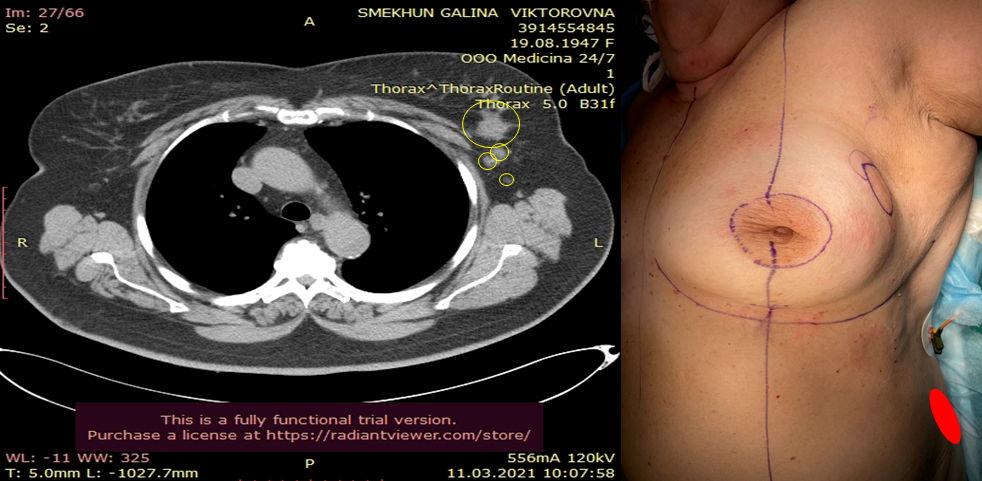

Инвазивный люминальный тип

Инвазивный люминальный тип 115 фото